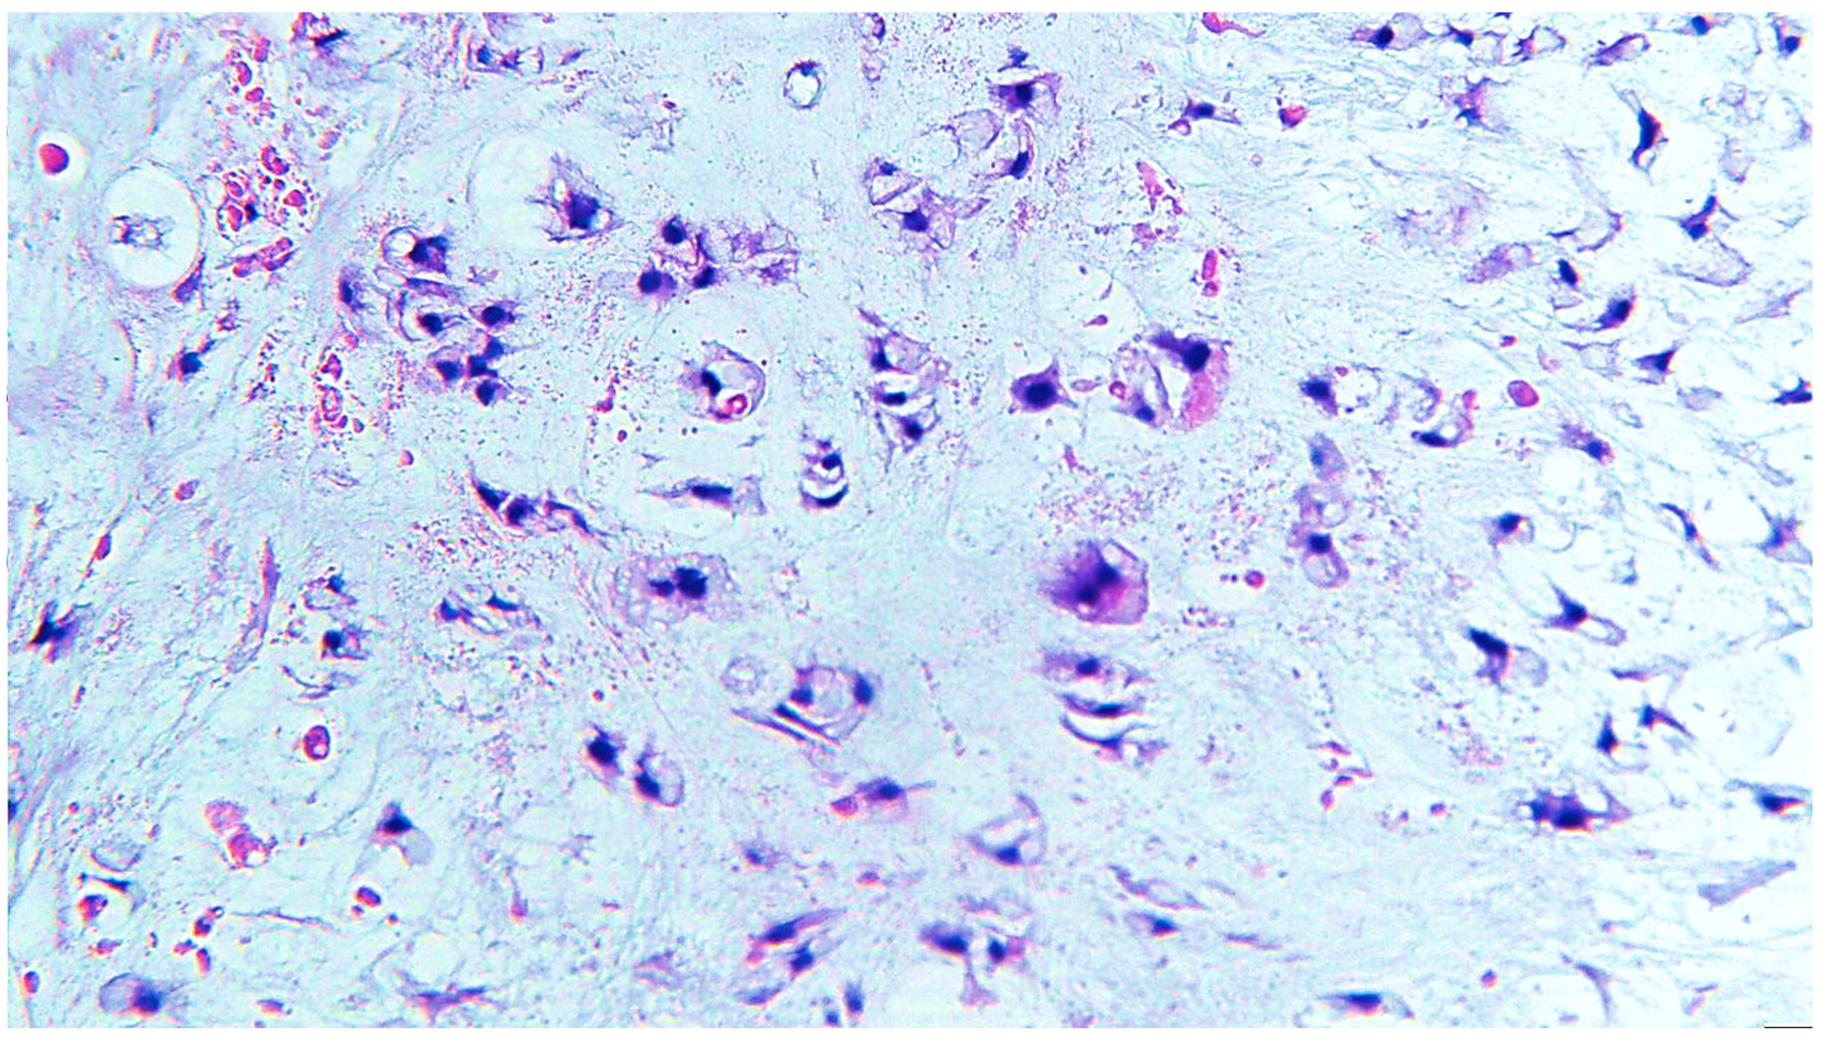

2. Clinical Case